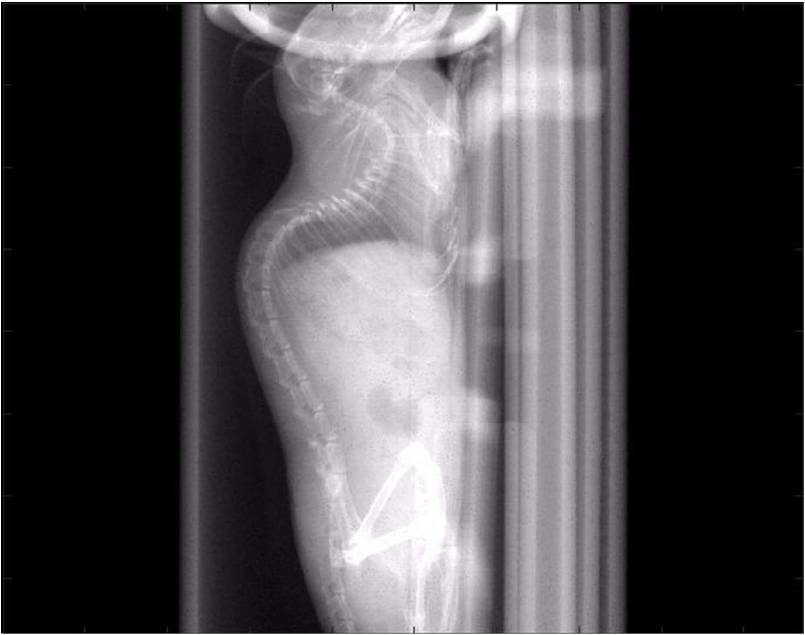

檢測(cè)案例

腫瘤血管生成

肺轉(zhuǎn)移

小鼠模式,22.5μm像素

正常

8天 14天

無(wú)造影劑注入 造影劑注入